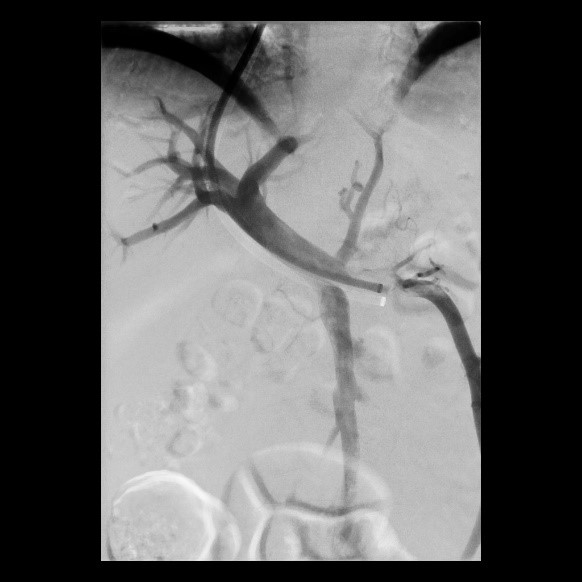

Postoperative abdominelle Blutungen bei chronischer Pankreatitis (Pfeile: Art. hepatica und Art. gastroduodenalis).

(Bild 1 von 5)

Postoperative abdominelle Blutungen bei chronischer Pankreatitis vor Embolisation der Art. gastroduodenalis mittels Metallspiralen (Coils)

(Bild 2 von 5)